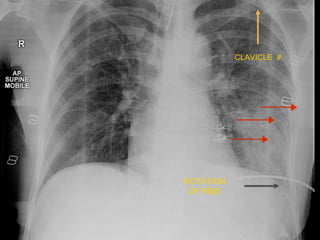

CLAVICLE #

ROTATION

OF RIBS

L O OK C A R E F U L L Y L E T S T R Y O N E M O R E

• 6.